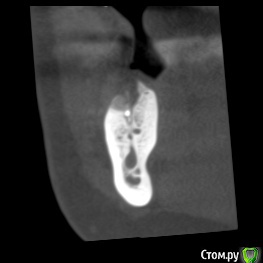

dentikl Опубликовано 26 ноября, 2019 Поделиться Опубликовано 26 ноября, 2019 В августе планировали имплантацию отсутсвующего 46 .Сделали кт,почистили .3 месяца. Ждать или уже ставить? Ссылка на комментарий

dentikl Опубликовано 26 ноября, 2019 Автор Поделиться Опубликовано 26 ноября, 2019 +1 ставитьто,что на первом скане -это коллатерали которые усложняют прогноз? Ссылка на комментарий

red_butler Опубликовано 26 ноября, 2019 Поделиться Опубликовано 26 ноября, 2019 то,что на первом скане -это коллатерали которые усложняют прогноз?Похоже 1 Ссылка на комментарий